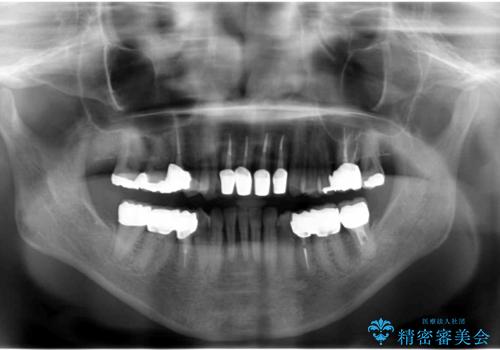

- 上顎前歯の黒ずみの改善、下顎前歯の十度なガタつき、矯正治療とセラミック治療を含む全体的な治療を希望され来院されました。

銀歯を高強度の仮歯に替えたのち、下顎前歯のみの部分矯正→全体的なマウスピース矯正治療(インビザライン)→最終的なセラミック治療と治療を進めます。

矯正治療と目立つ銀歯のやりかえを行ったことでかみあわせだけでなく、審美性・清掃性も改善し口腔内の環境を劇的に改善することができました。